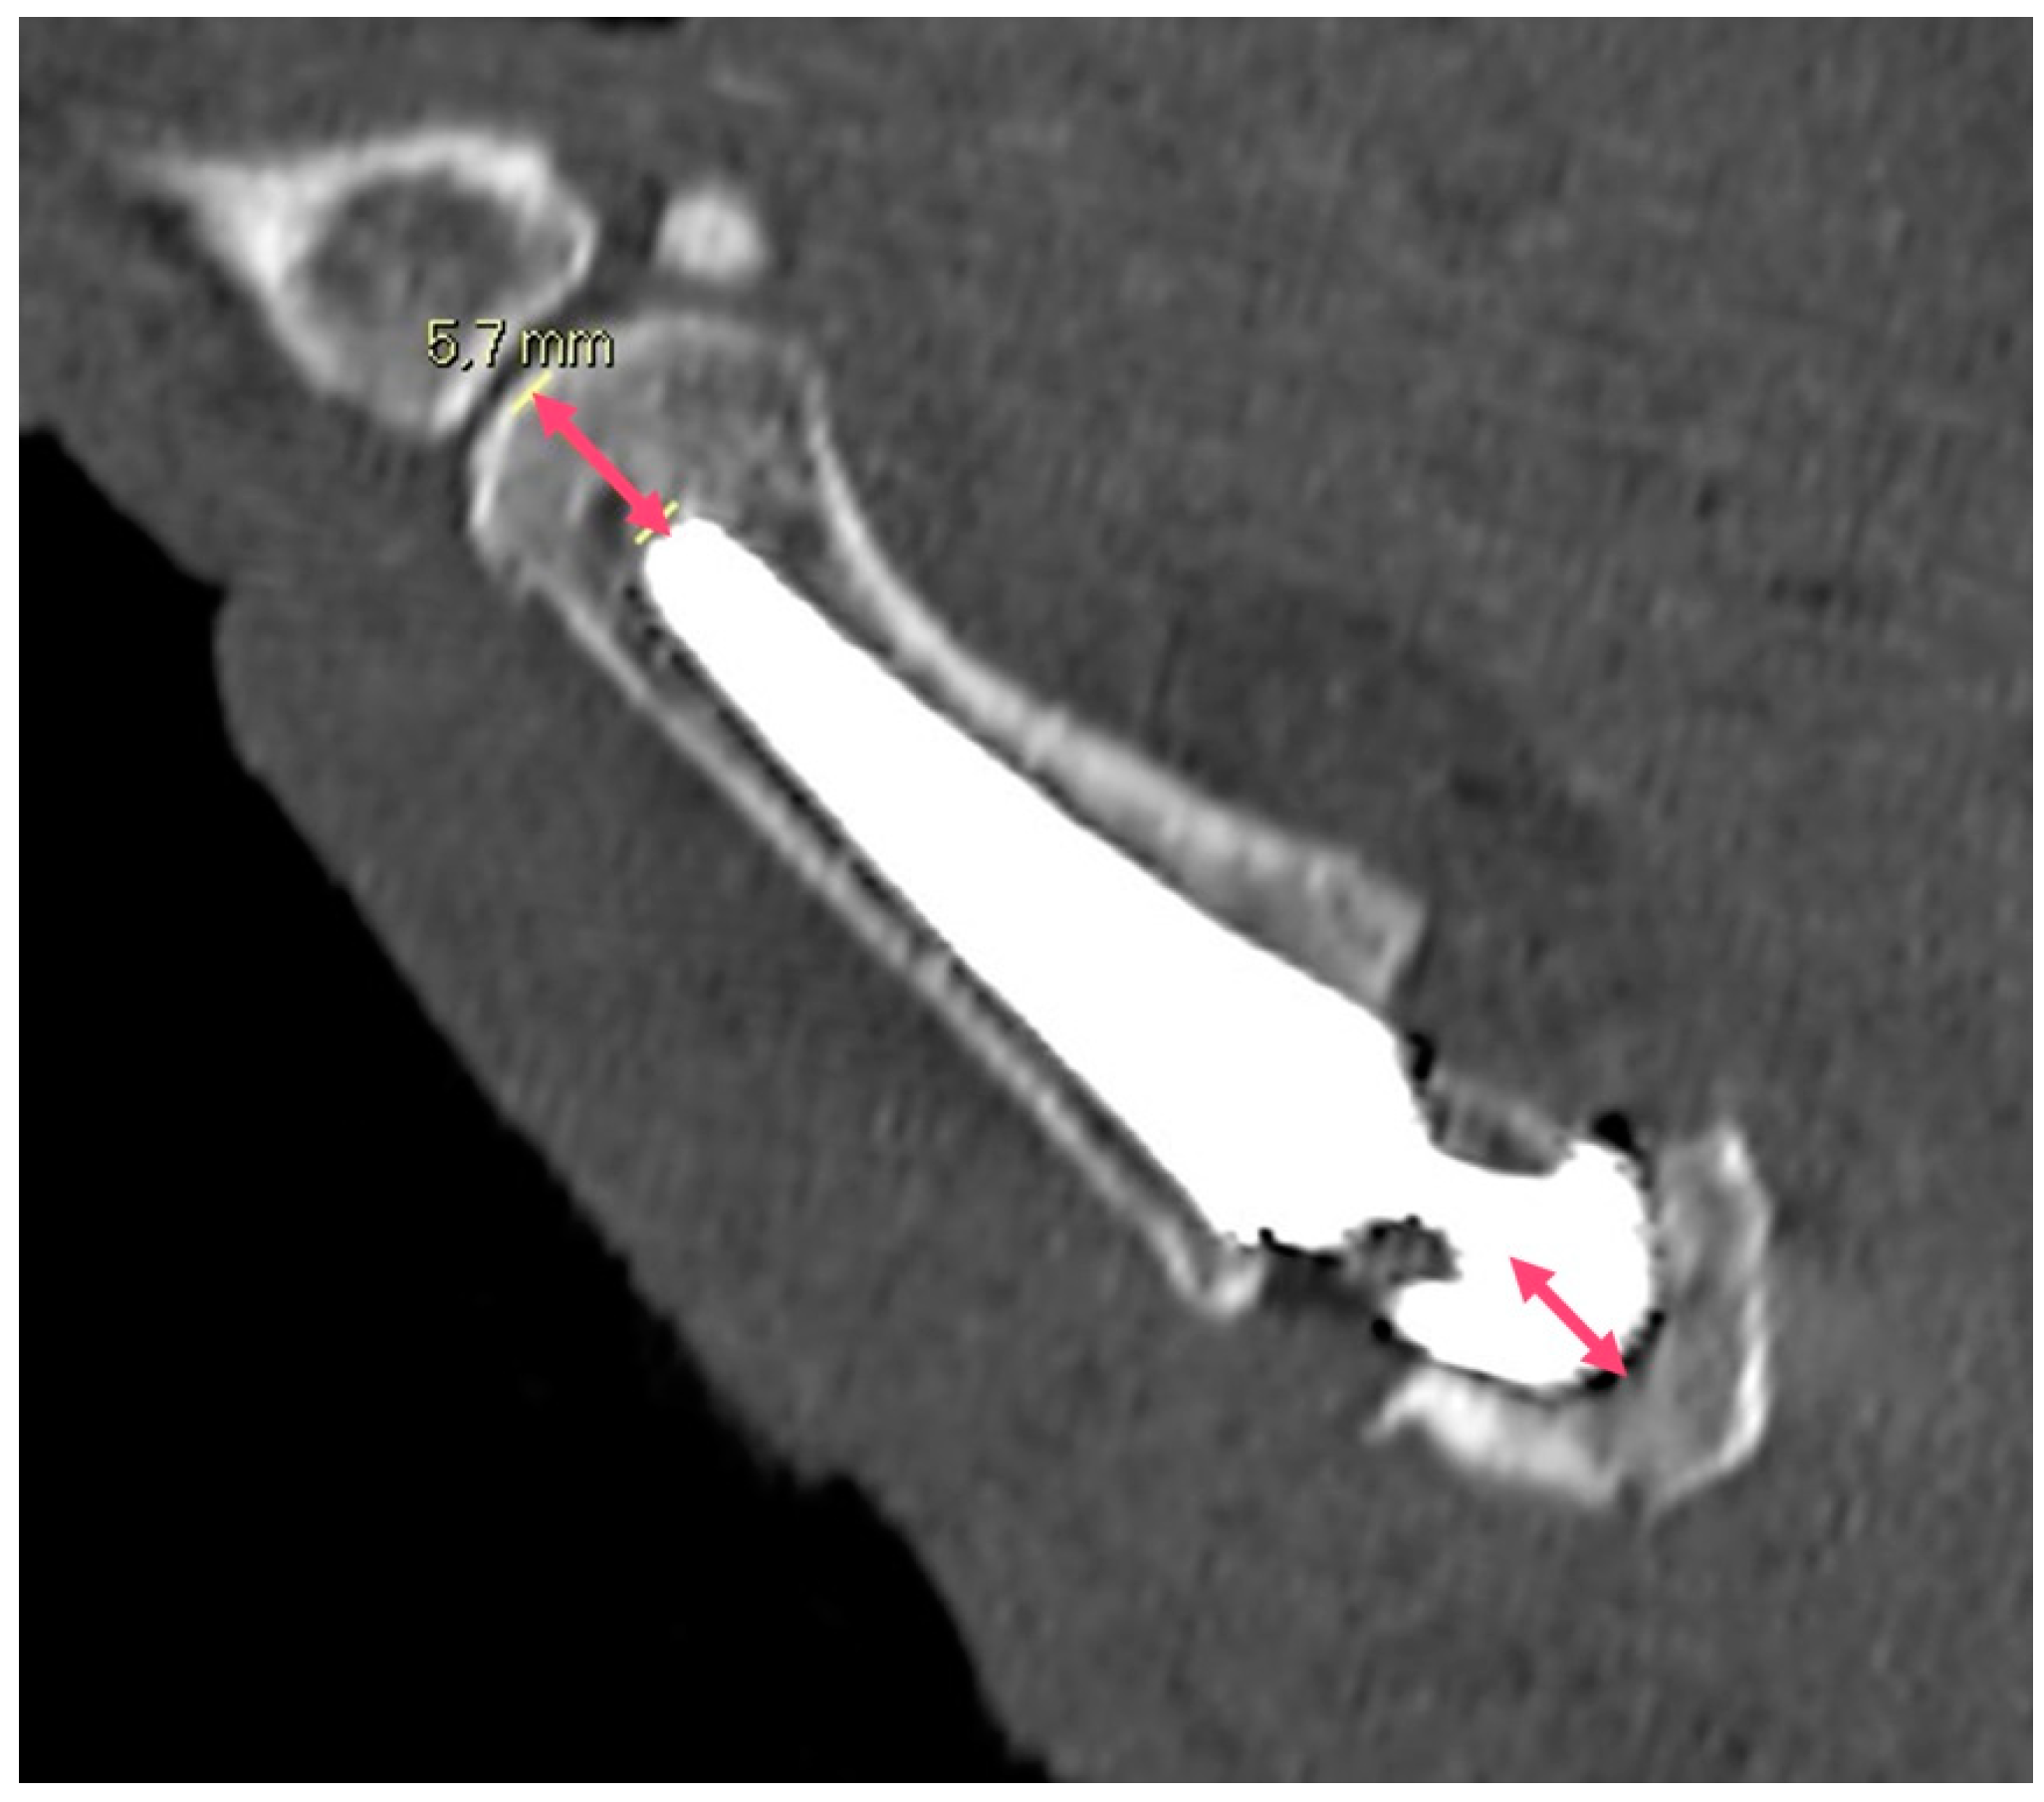

2.5. Imaging Analysis

3.1. CT Results

| Angle between the prosthesis axis and the M1 axis | 2.8° | ±1.3° |

| Metacarpal index | 11.3 | ±3.3 |

| Trapezium index | 4.5 | ±0.1 |

| Angle between the cup distal surface and the trapezium | 2.0° | ±3.7° |

| Distance between the center of the trapezium and the center of the cup | 2.2 mm | ±1.3 mm |